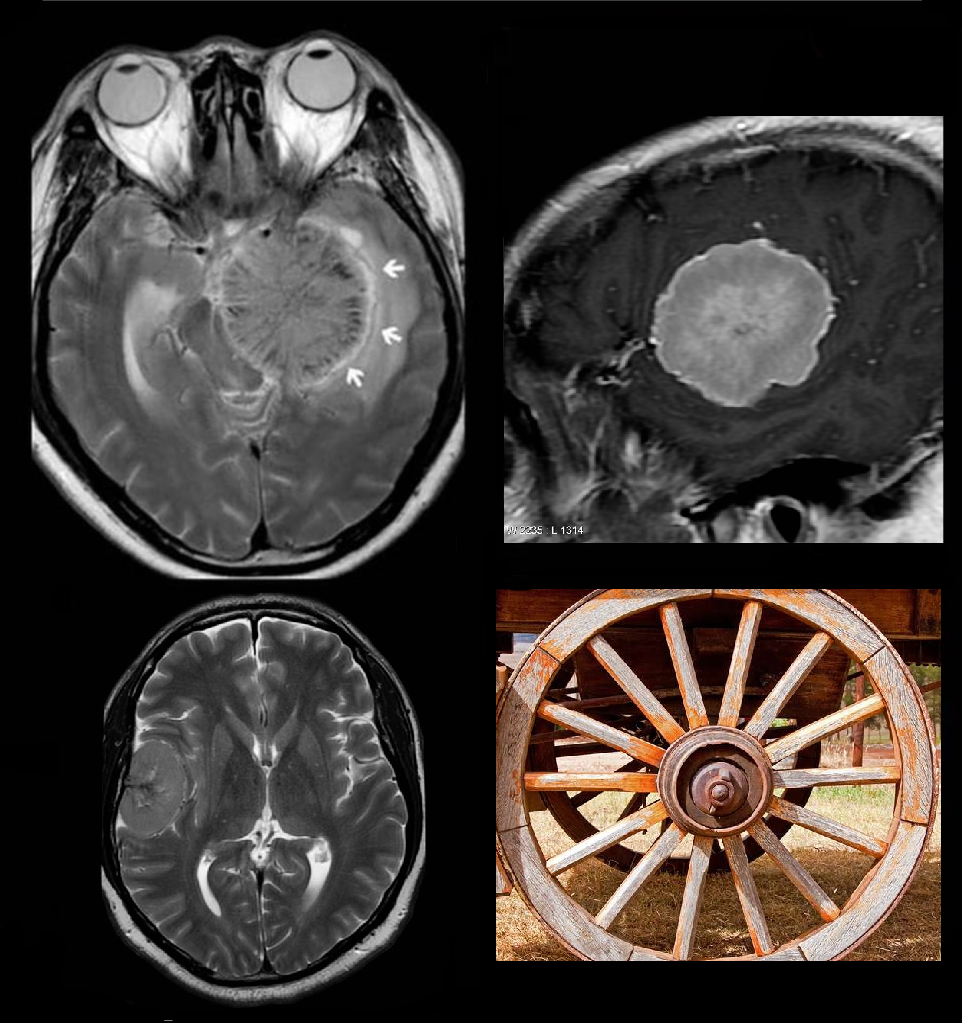

🔸МРТ-феномен «колесо со спицами»

#ТелеМед_интересные_факты 😮А вы знали, что при менингиоме на МРТ-изображениях можно увидеть такой симптом, как «колесо со спицами»? 🦠Это происходит за счет рисунка сосудов, проходящих через менингиому, при её рассмотрении в поперечном сечении. Тот же сосудистый рисунок приводит к появлению паттерна солнечных лучей☀️, когда сосуды видны сбоку, а не в поперечном сечении. 📍Классически центральная область менингиомы кровоснабжается дуральными питающими сосудами в месте прикрепления к твёрдой мозговой оболочке, в то время как капсула питается пиальными или корковыми питающими сосудами. 🔵Именно питающие артериальные ветви, расходящиеся в образовании радиально, создают вид колеса со спицами на Т2-взвешенных изображениях, или постконтрастных изображениях, или во время ангиографии🔍. 📌Также внешний вид колеса со спицами может наблюдаться при опухоли почек (например, онкоцитоме). #МРТ #колесо #спицы #менингиома

😮А вы знали, что при менингиоме на МРТ-изображениях можно увидеть такой симптом, как «колесо со спицами»? 🦠Это происходит за счет рисунка сосудов, проходящих через менингиому, при её рассмотрении в поперечном сечении. Тот же сосудистый рисунок приводит к появлению паттерна солнечных лучей☀️, когда сосуды видны сбоку, а не в поперечном сечении.

📍Классически центральная область менингиомы кровоснабжается дуральными питающими сосудами в месте прикрепления к твёрдой мозговой оболочке, в то время как капсула питается пиальными или корковыми питающими сосудами. 🔵Именно питающие артериальные ветви, расходящиеся в образовании радиально, создают вид колеса со спицами на Т2-взвешенных изображениях, или постконтрастных изображениях, или во время ангиографии🔍.

📌Также внешний вид колеса со спицами может наблюдаться при опухоли почек (например, онкоцитоме).